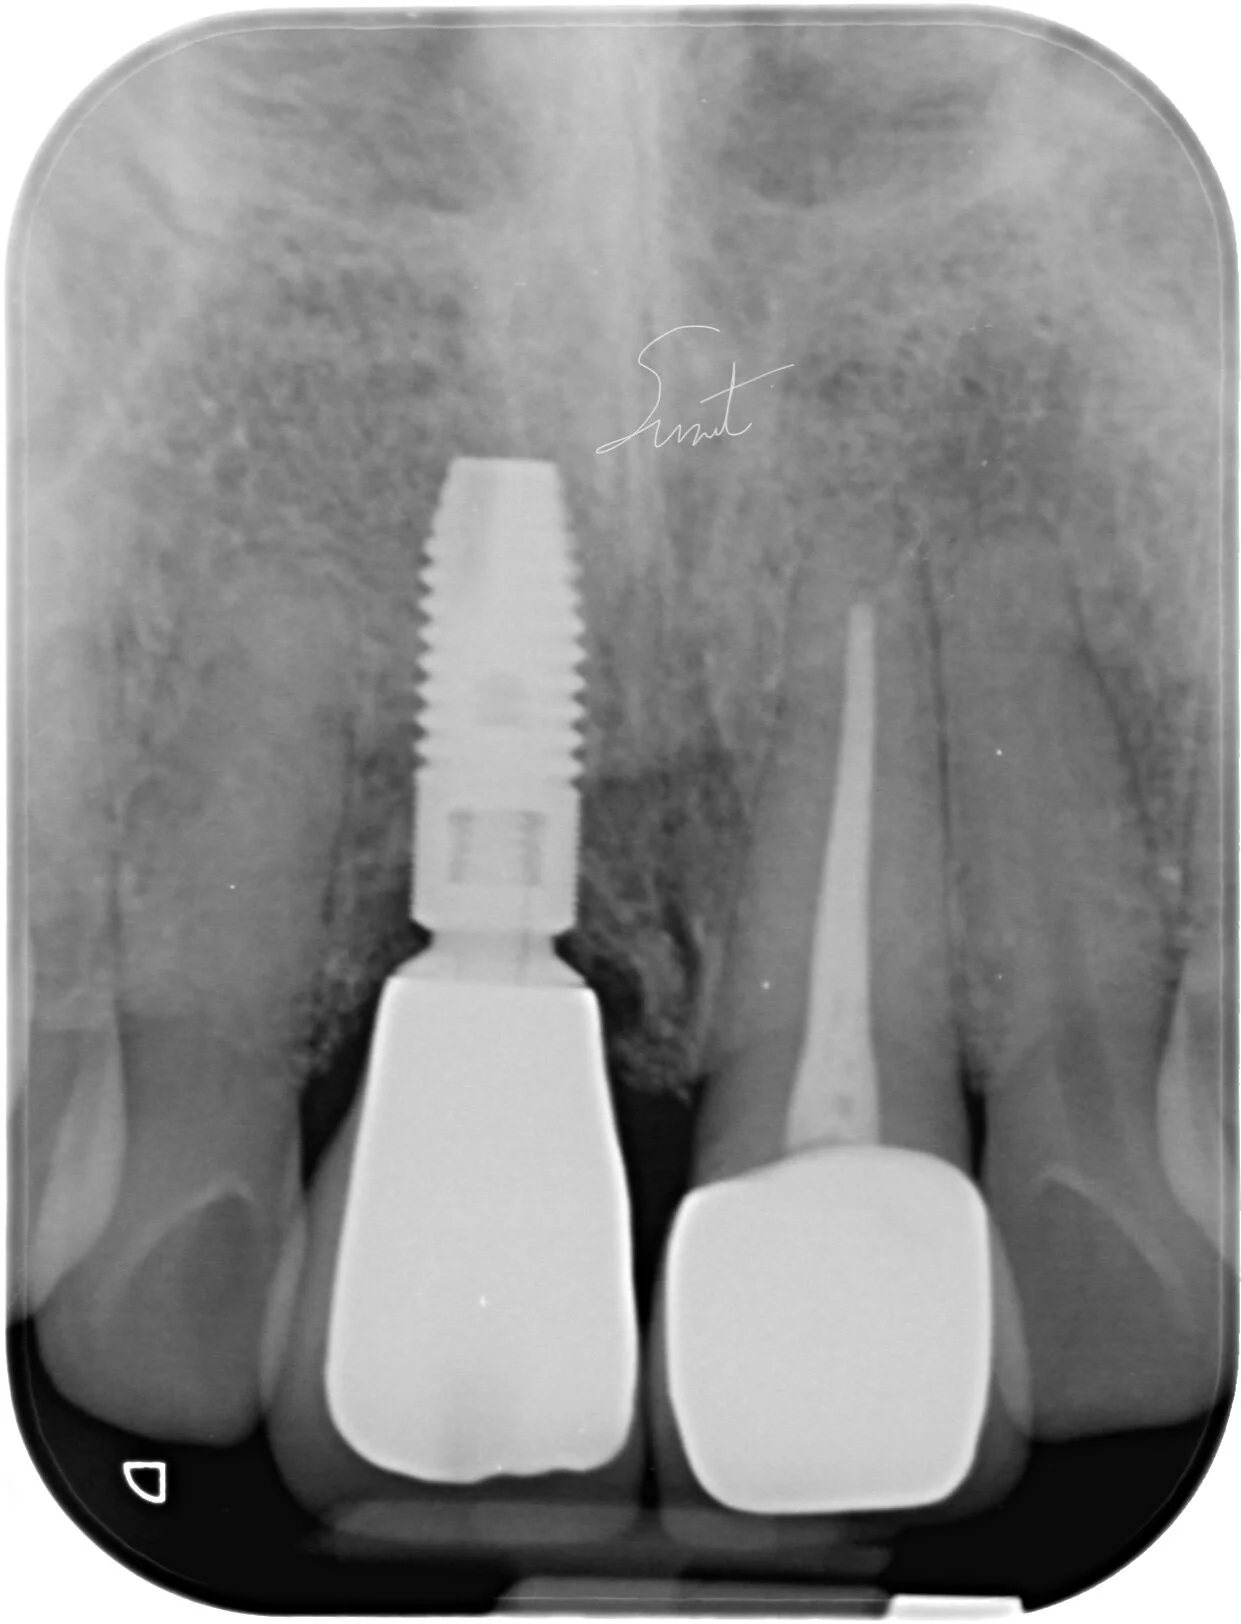

การปวดฟัน มีหลายแบบ เช่น อาการปวดฟันที่เล็กน้อย หรือปวดแบบรุนแรง จนบางครั้งรุนแรงจนนอนไม่หลับ อาจมีอาการปวดฟันโดยไม่มีสิ่งกระตุ้น หรือปวดเวลามีสิ่งกระตุ้นเช่นตอนเคี้ยวอาหาร บางกรณีมีเหงือกบวม หรือมีหนองซี่ที่ปวดร่วมด้วย รวมถึงการมีฟันสีคล้ำผิดจากฟันซี่อื่น และมีอาการเสียวฟันจากความเย็นหรือความร้อนซึ่งอาการเหล่านี้เป็นอาการเตือนในเบื้องต้นว่า มีการอักเสบของเนื้อเยื่อประสาทฟัน นอกจากนี้ยังมีบางกรณีที่ไม่มีอาการใดๆ เตือนให้รู้เลย มารู้ตัวอีกทีก็คือฟันโยกจนเกือบจะหลุด หรือฟันแตกหักรุนแรง เหลือแต่รากฟันเท่านั้น หากพบว่าตัวคุณมีอาการเหล่านี้ ควรปรึกษาทันตแพทย์ เพื่อตรวจ และเอ็กซ์เรย์ฟัน ซึ่งทันตแพทย์จะสามารถวินิจฉัยอาการของโรค และวางแผนการรักษาให้กับคุณได้

การรักษารากฟัน บางกรณีสามารถรักษาให้เสร็จภายในครั้งเดียวได้ ทั้งนี้จะขึ้นอยู่กับสภาพของฟันว่ามีการอักเสบมากน้อยแค่ไหน ฟันที่รักษารากฟันแล้วควรได้รับการสังเกตุอาการไปอีกช่วงระยะเวลาหนึ่ง เพื่อให้แน่ใจว่าโรคที่เกิดขึ้นบริเวณปลายรากฟันหายดีเป็นปกติแล้ว บางคนอาจรู้สึกปวดฟันหรือเสียวฟันเล็กน้อยได้ใน 2-3 วันแรกหลังการรักษารากฟัน โดยทันตแพทย์จะให้ทานยาแก้ปวด ร่วมกับยาแก้อักเสบเพื่อบรรเทาอาการ ซึ่งอาการปวดนี้ก็จะค่อยๆ หายไปได้เอง แต่อาจจะต้องใช้เวลาสักระยะ หมั่นคอยดูแลทำความสะอาดช่องปากอย่างสม่ำเสมอ และงดใช้งานฟันซี่ที่ยังอยู่ในขั้นตอนการรักษา ห้ามเคี้ยวอาหารที่มีลักษณะเหนียวหรือแข็ง เพราะอาจจะทำให้ฟันแตกได้